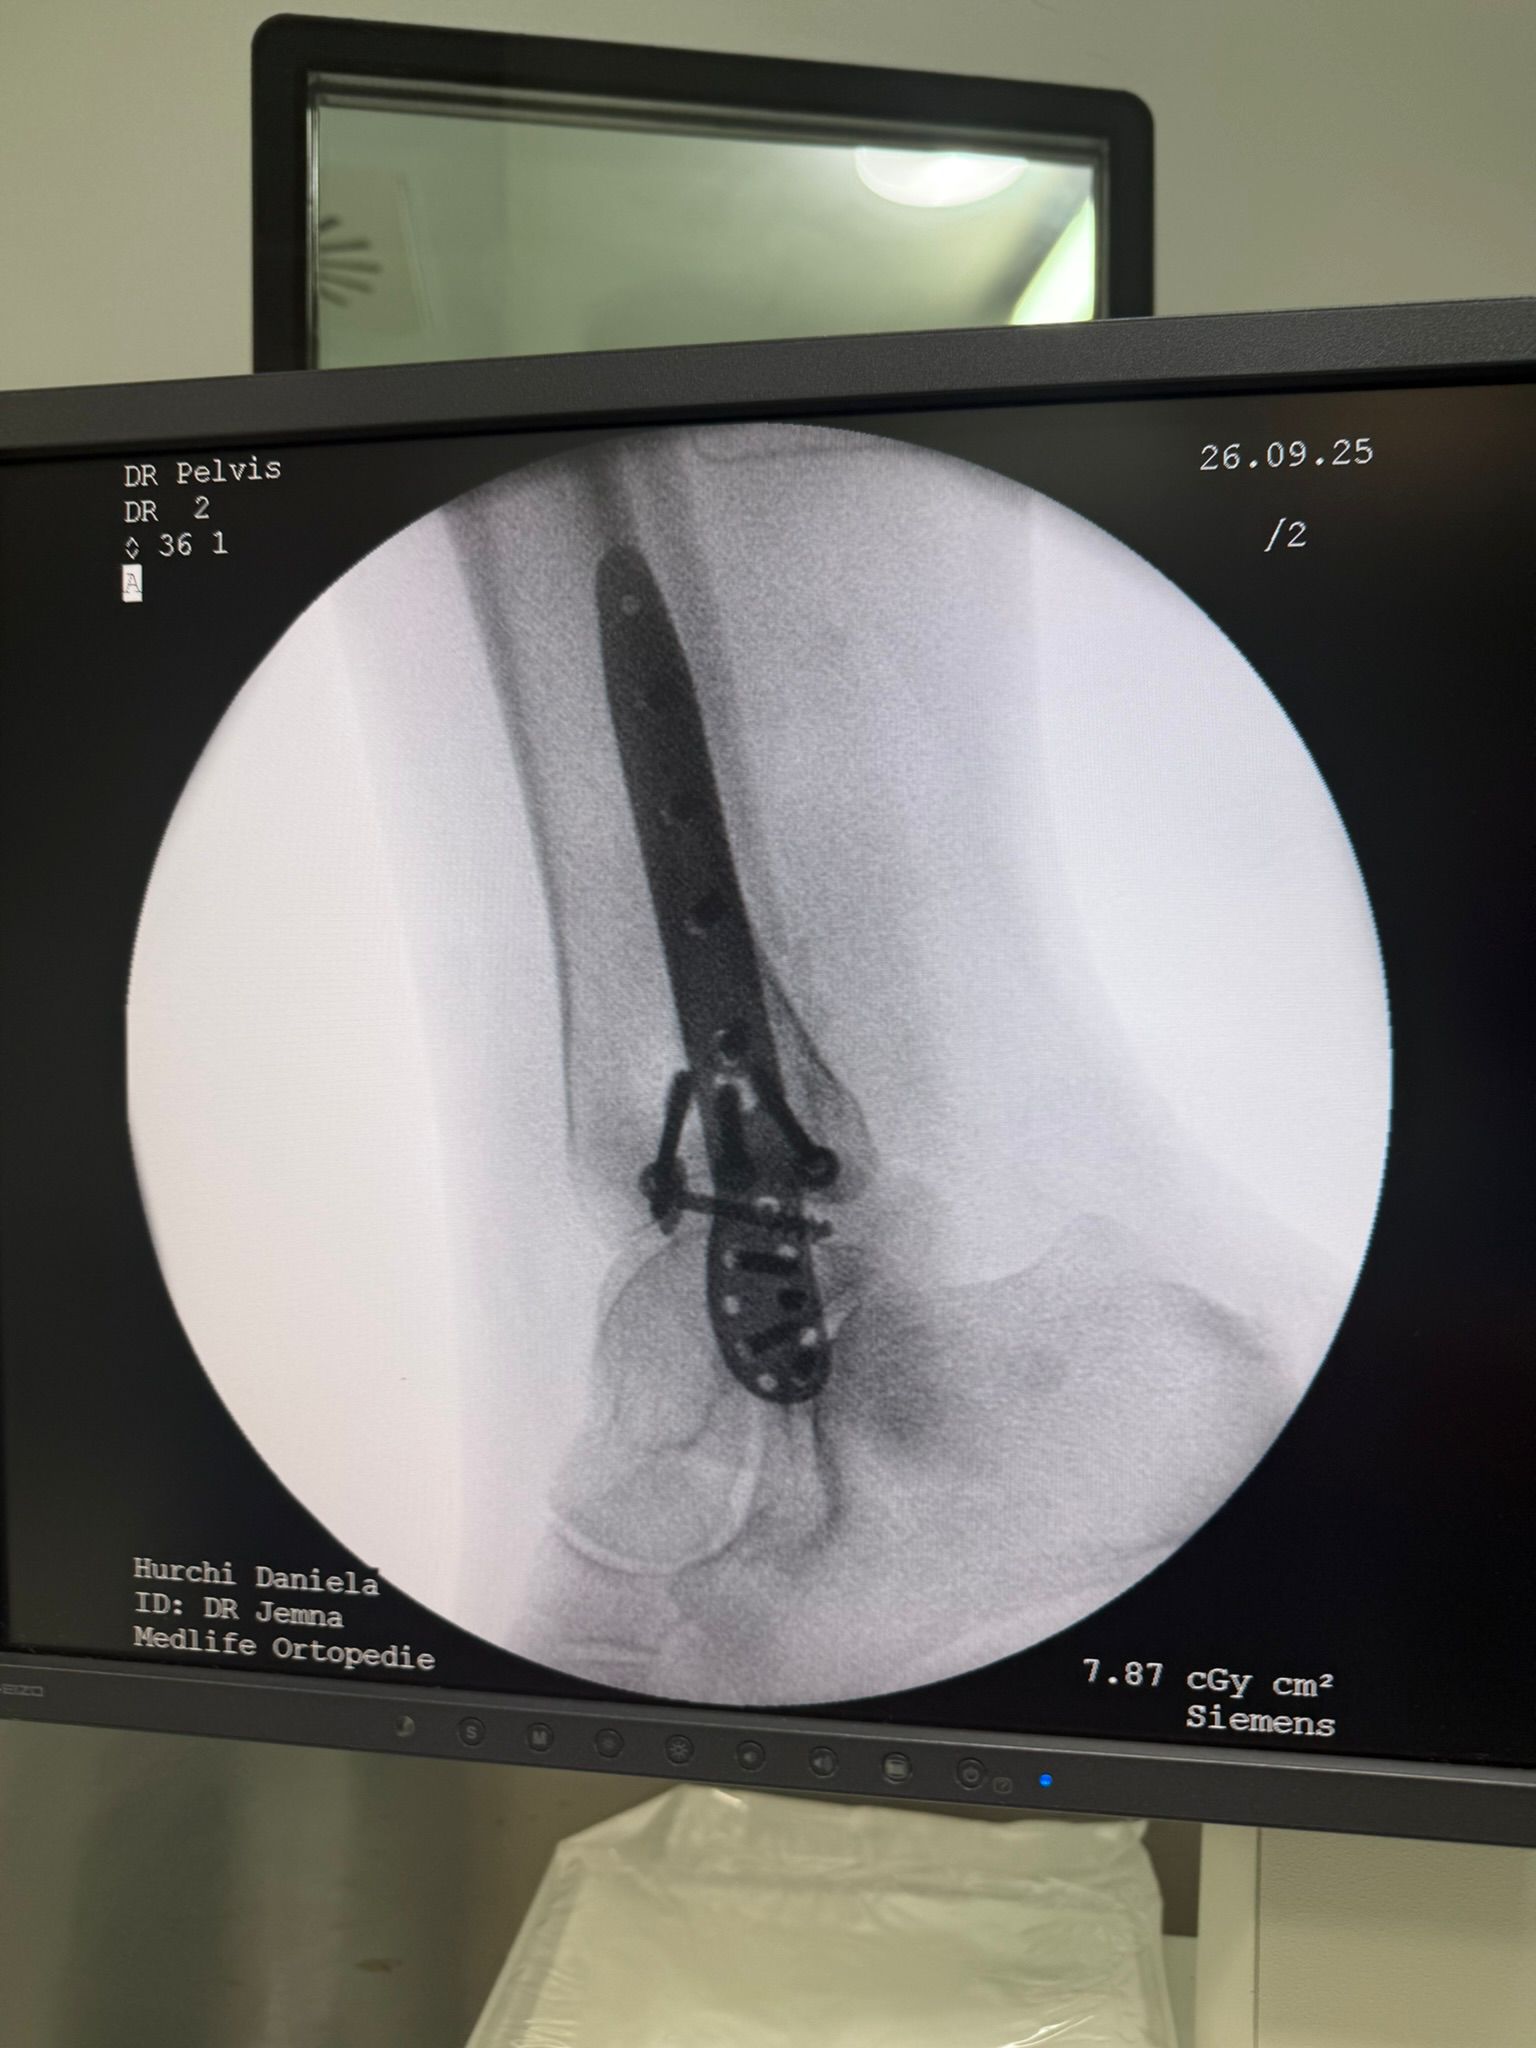

Imagini Clinice